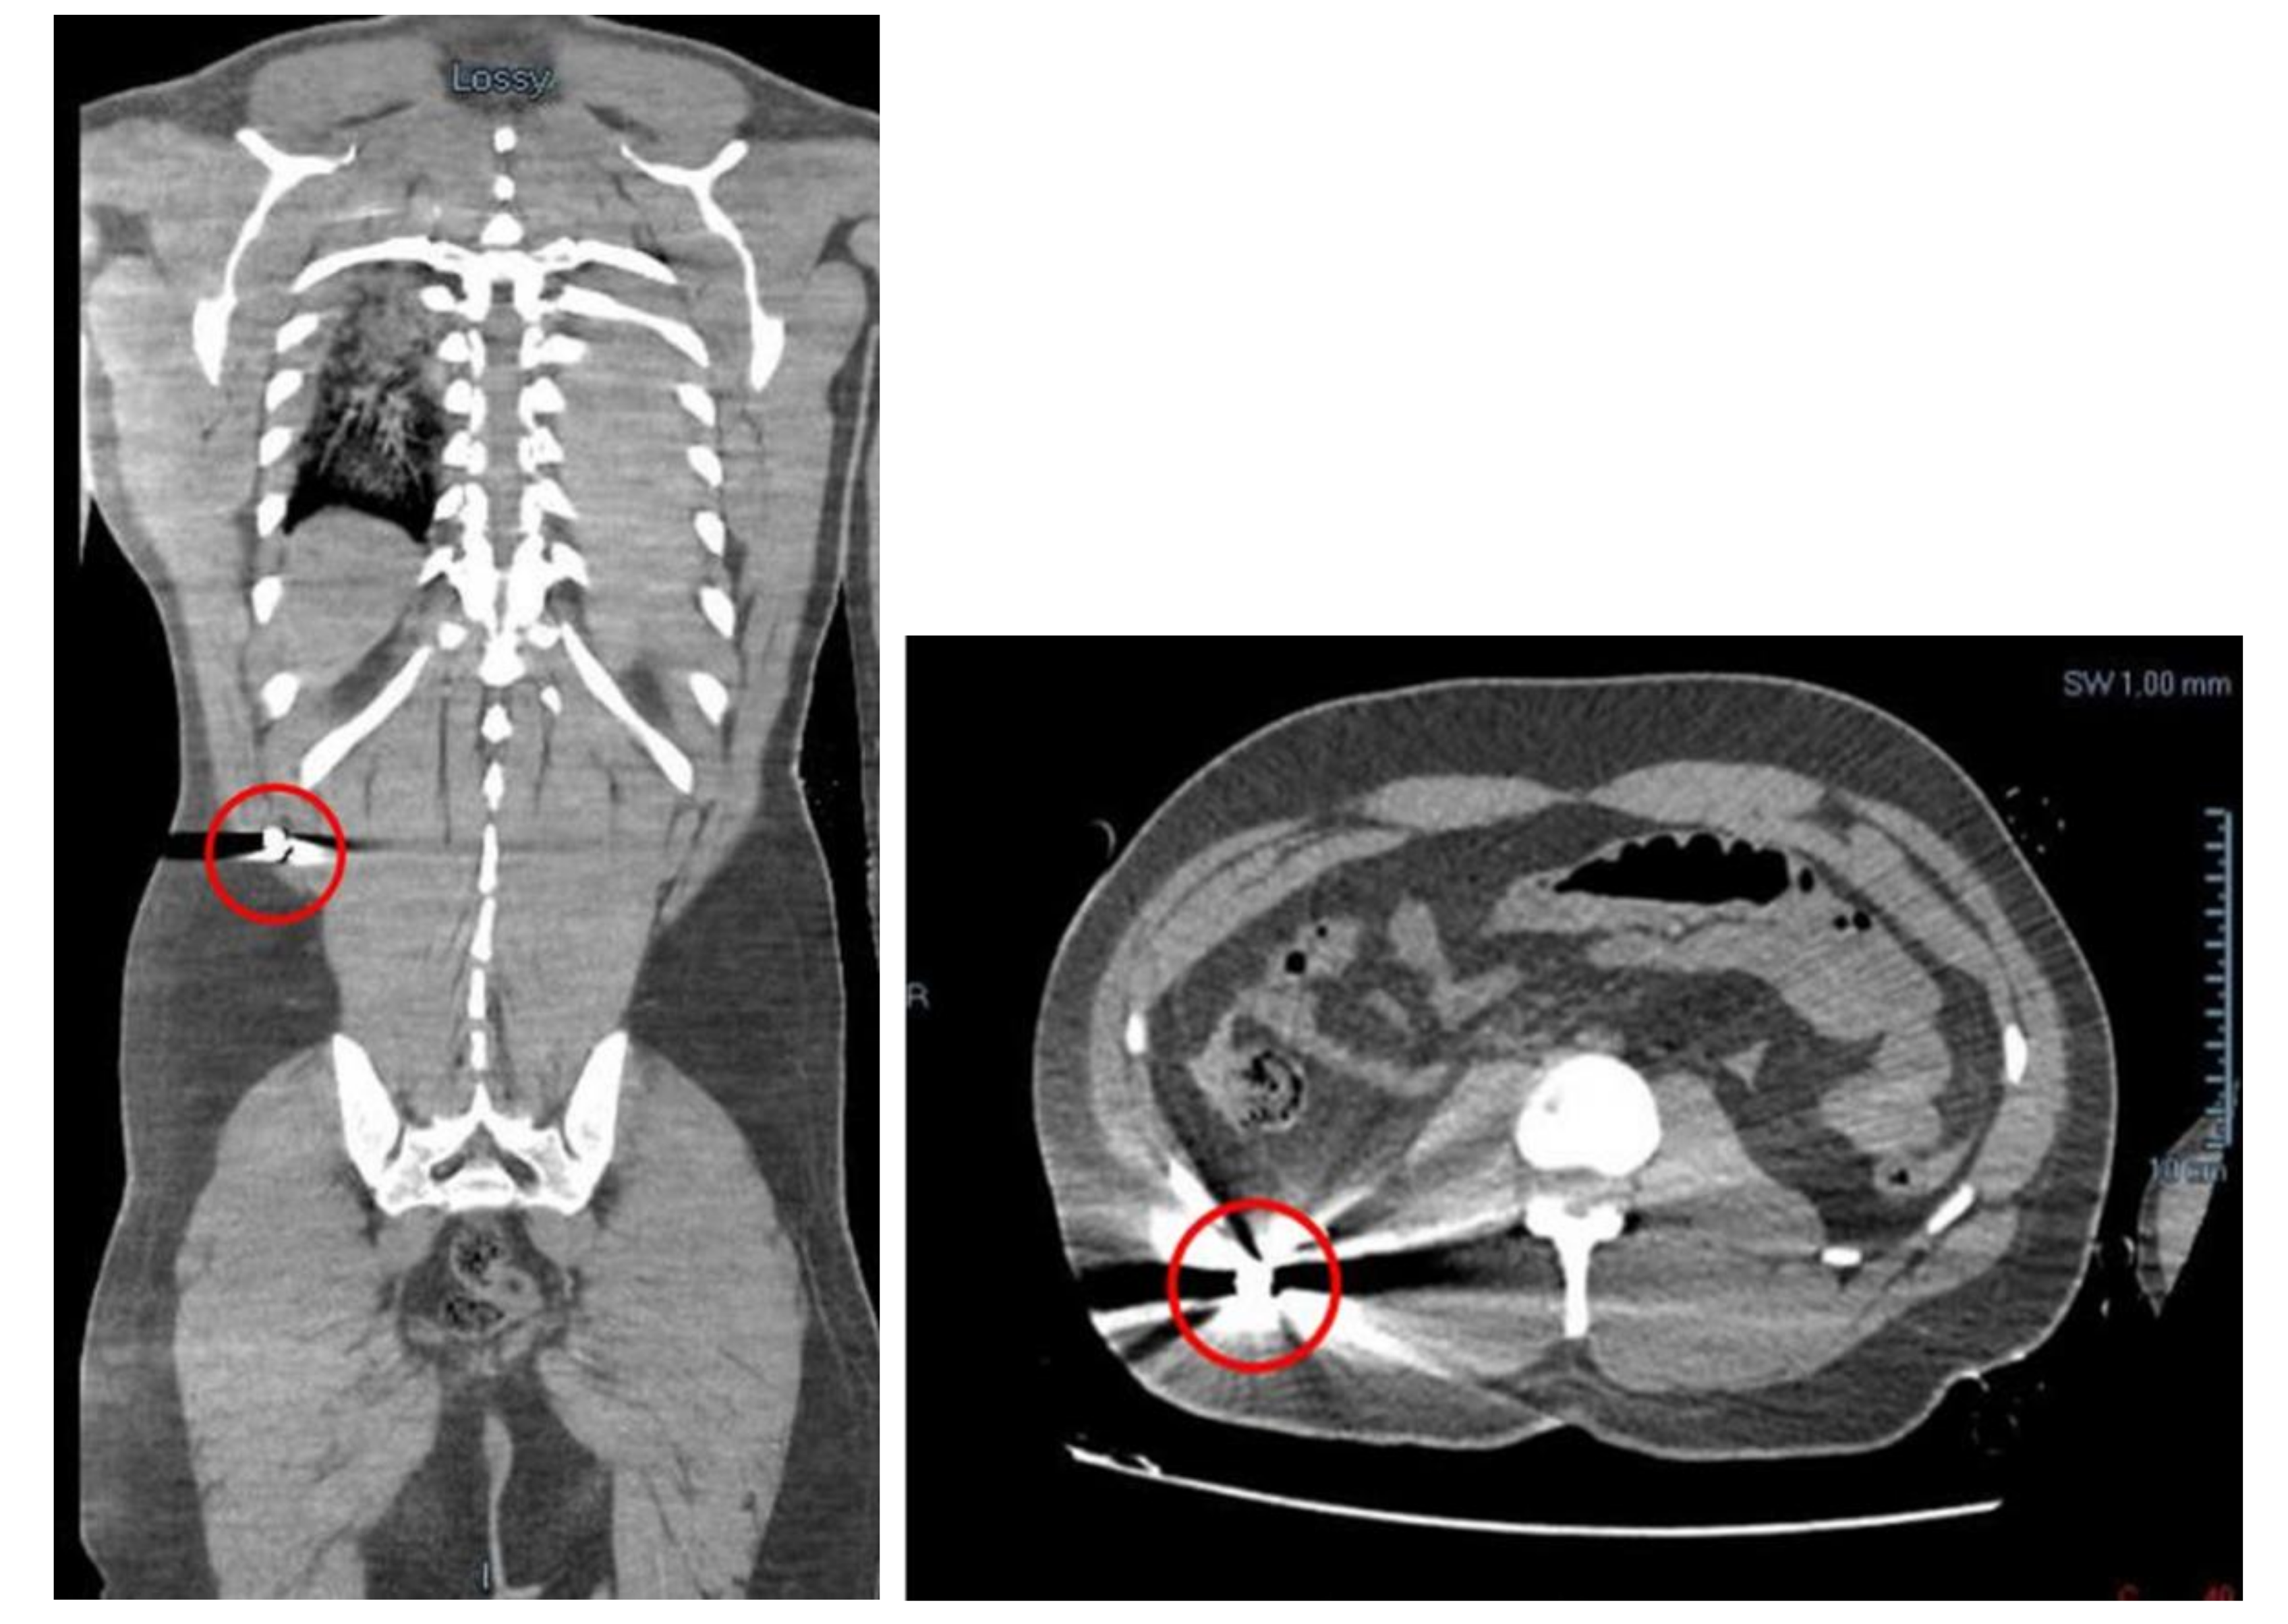

Before the autopsy, a full-body CT was performed. It was found a massive left hemothorax and free air at the level of the left hemithorax itself and of the homolateral subclavear and pectoral regions. More free air was found in the mediastinal area and small bubbles in the ventricles were detected. There were also an haemopericardium (with a thickness of 2 cm) and an hemomediastinum. Moreover, little bubbles were found in the hepatic parenchyma and in the left anterior abdomen. A liquid effusion was detected in the subcapsular area of the liver, in the Morrison’s pouch, in the subcapsular region of the right kidney and in the pelvic area. In the right lateroposterior extra-abdomen area, in the homolateral external oblique muscle and on the subcutaneous side, there was a small and hyperdense image, identifiable in a projectile’s ogive of 9 mm caliber. The external oblique muscle has traumatic lesions (Figure 2). In the end, a projectile’s path has been appreciated in the subcutaneous region of the antero-inferior abdominal surface, with a cutaneous entrance GSW on the right anterolateral abdominal surface and an exit one on the left anterolateral side.

Figure 2.

The retained bullet in the thickness of the posterior abdominal wall.